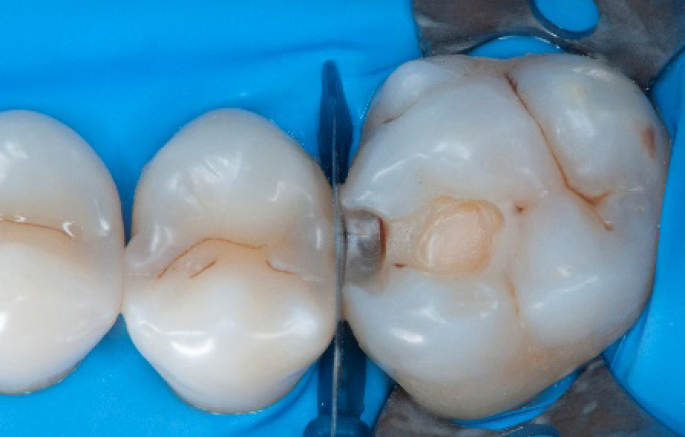

Step 12:

The situation after rubber dam removal.

Step 13:

Occlusal check

Step 14:

2 weeks control